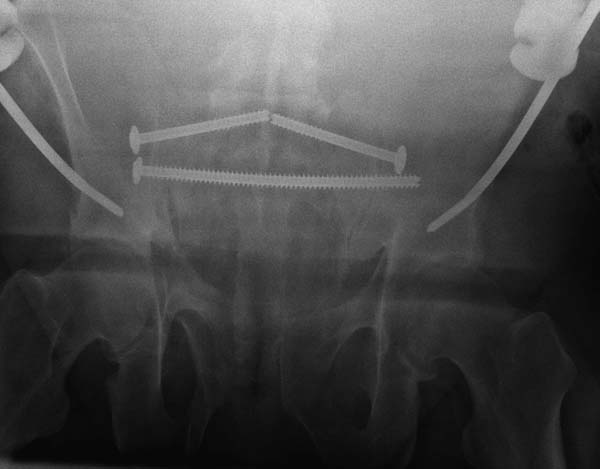

Здесь примеры фиксации с различными вариантами.... .

Здесь снимки, которые показывают направление стержня, а также идею репозиции вытяжением. На рентгенопроницаемых столах имеется возможность установить дополнительную раму, где по желанию можно увеличить или уменьшить высоту угла вытяжения. Для репозиции таза больной в положение на спине, стержень для вытяжения остается во время операции. Система подойдет для тракции головки бедра из вертлужной впадины, и для этого стерильная веревка и Synthes Universal Chuck with T-Handle.

Двухстороннее повреждение крестца и травматическая ампутация бедра, где неопытной бригадой дежурантов установлен верхний наружный фиксатор для стабилизации. На третий день ревизия на более стабильный, и окончательная фиксация. Первые снимки после стабилизации таза, и другие, где показаны (параллельные) правильная установка на AIIS т.е на месте прикрепления прямой мышцы бедра. Ампутация закончена костно пластическим методом.

Большое спасибо всем Вам за помощь! Вчера прооперировали пациентку. Выполнили закрытую репозицию левой половины таза на тракционном столе под контролем ЭОП, закрытая фиксация левого КПС двумя каннулированными винтами. Учитывая удовлетворительное стояние отломков лонной и седалищной костей справа, а так же удовлетворительную ширину лона передние отделы стабилизировали системой ЦИТО

Послеоперационные КТ прилагаются

Винты введены в S1